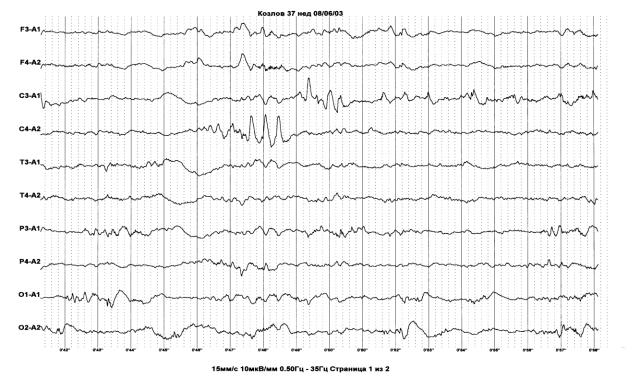

6.4. Электроэнцефалография

Выполнение динамических электроэнцефалографических исследований у недоношенных детей с ПИВК необходимо для интегративной оценки функционального состояния головного мозга младенцев в остром периоде инсульта, дифференциального диагноза эпилептических и неэпилептических пароксизмов, выявления эпилептиформной активности и прогнозирования отдаленных исходов нервно-психического развития детей.

Изменения базовой (фоновой) активности на ЭЭГ недоношенных в острой стадии при различных по этиологии церебральных инсультов во многом неспецифичны и отражают степень и тяжесть дисфункции головного мозга новорожденного ребенка. Увеличение средней продолжительности инактивных межвспышечных интервалов – tracé discontinu, стойкая фокальная или диффузная депрессия амплитуды ритмов, значимое уменьшение представленности на ЭЭГ транзиторных комплексов, например, « -щеток», нарушение формирования в динамике паттернов стадий цикла сон/бодрствование, присутствие эпилептиформной активности и избыточного количества «позитивных роландических и темпоральных спайков» – наиболее важные электрографические критерии церебральной дисфункции у недоношенных детей в остром периоде ишемически-геморрагических инсультов, которые нередко соотносятся с неблагоприятным исходом.

Патологоанатомические исследования недоношенных с ПИВК показали, что степень выраженности изменений на ЭЭГ отчетливо коррелирует с распространенностью поражения мозга (Aso K. и соавт., 1993). Показано так же, что выраженная депрессия активности, удлинение периодов «электрического молчания» trace discontinu (особенно более одной минуты) и эпилептиформная активность соотносятся со степенью тяжести неблагоприятных исходов при интравентрикулярных геморрагиях (Clancy R. и соавт., 1984; Greisen G. и соавт.,

1987; Benda G. и соавт., 1989).

Описанные Cukier F. (1972) «позитивные роландические и темпоральные спайки» на неонатальной ЭЭГ, превоначально соотносили с внутрижелудочковыми кровоизлияниями. Однако более поздние энцефалографические исследования в сопоставлении с данными аутопсии и нейровизуализации показали, что необычные по морфологии и характерной локализации одиночные острые волны патогномоничны для паренхиматозного (перивентрикулярного) поражения мозга недоношенных детей и напрямую не ассоциируются с изолированными интравентрикулярными кровоизлияниями (Clancy R. и соавт., 1984; Marret S. и

соавт., 1992). В настоящее время не установлены специфические электрографические маркеры изолированных внутрижелудочковых геморрагий.

Избыточное количество «позитивных роландических и темпоральных острых волн», стойкая унилатеральная амплитудная депрессия, уменьшение регистрации « -щеток» над одним из полушариев и фокальная эпилептиформная активность («электрографические судороги», комплексы BIRD) нередко встречаются у детей с внутрижелудочковыми геморрагиями, осложнившимися перивентрикулярным геморрагическим инфарктом (Понятишин А.Е и соавт., 2006;

Aso K. и соавт., 1993) (рис. 12)

Рис. 12. Постменструальный возраст 37 недель. ПИВК II ст. и сопутствующая ПВЛ (кистозная стадия). На ЭЭГ в центральных отделах регистрируются «позитивные острые волны».